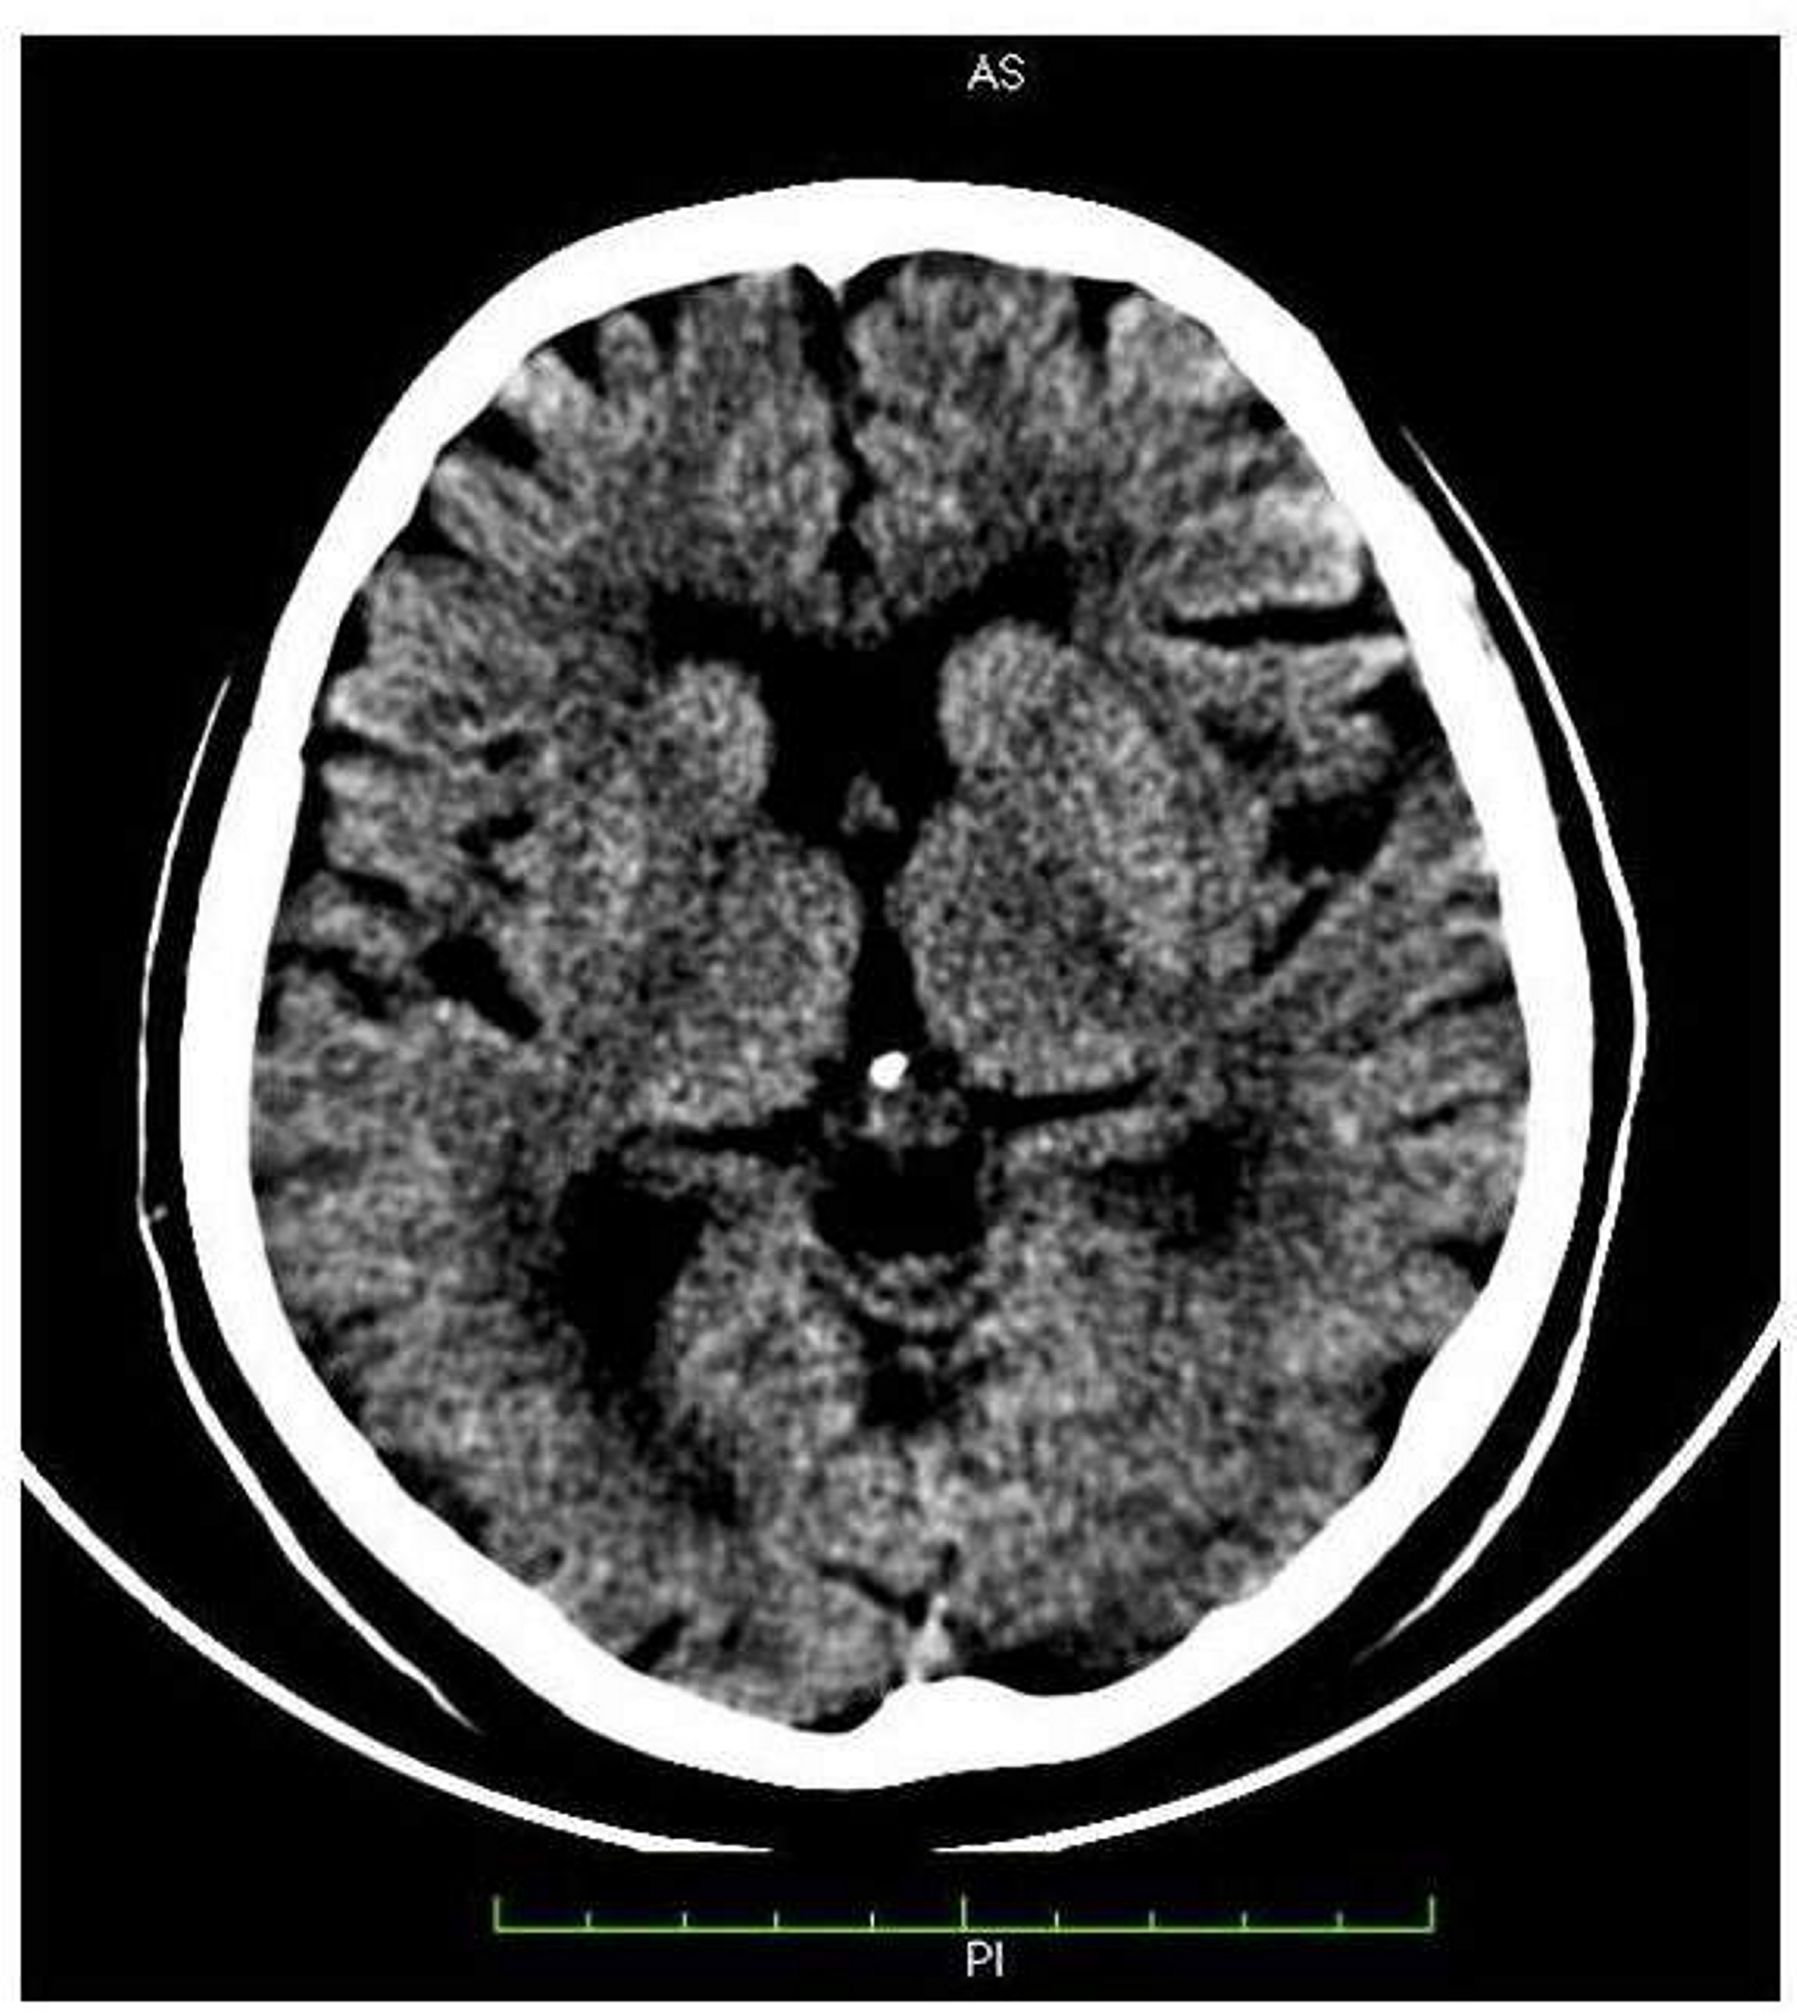

A hemicoreia-hemibalismo (HCHB) faz parte de um espectro de movimentos contínuos e involuntários de uma parte do corpo. Dentre as causas está o Diabetes mellitus. A apresentação de HCHB no estado hiperglicêmico configura-se como uma manifestação rara desse distúrbio metabólico sistêmico, e é associado a alterações nos exames de imagem cerebral, como a tomografia computadorizada, constituindo-se numa síndrome de caracterização e estudos recentes e de poucos relatos na literatura. Trata-se de uma paciente que apresentou abertura do quadro de Diabetes mellitus tipo 2 com HCHB, além de queixas de poliúria e polidipsia, apresentado, à admissão, glicemia capilar ao acaso de 586 mg/dl. A tomografia de crânio evidenciou leve hiperdensidade nos gânglios da base à direita. Após o controle dos níveis glicêmicos, a paciente apresentou melhora progressiva até remissão total do quadro em um período de 30 dias, com nova imagem tomográfica revelando completo desaparecimento da lesão neurológica inicial.